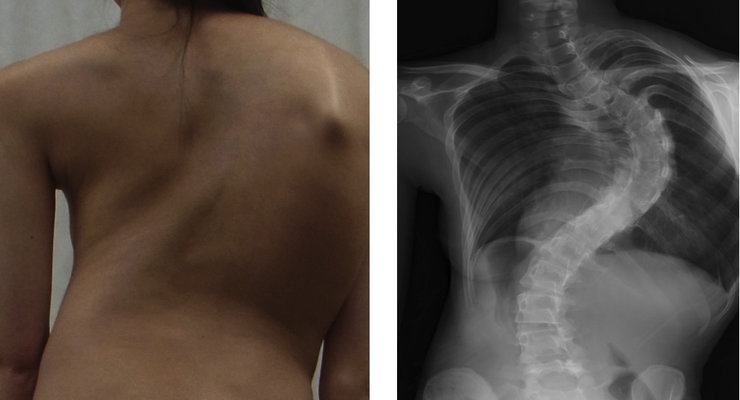

Οι νευρομυϊκές παθήσεις αποτελούν μια σειρά ετερογενών νοσημάτων όπως η νόσος του Parkinson, η σκλήρυνση κατά πλάκας και πολλές μυοπάθειες, που παρά το εντελώς διαφορετικό νοσολογικό υπόβαθρο έχουν σε μεγάλο βαθμό την ίδια κατάληξη. Οι παθήσεις αυτές εκτός από την δυσκολία που προκαλούν στον ασθενή στο περπάτημα, οδηγούν και στο σχηματισμό παραμορφώσεων της σπονδυλικής στήλης, οι οποίες μερικές φορές είναι πολύ σοβαρές. Οι παραμορφώσεις αυτές «εγκλωβίζουν» τους πνεύμονες μέσα στο θώρακα, με αποτέλεσμα να περιορίζεται αντίστοιχα και η πνευμονική λειτουργία.